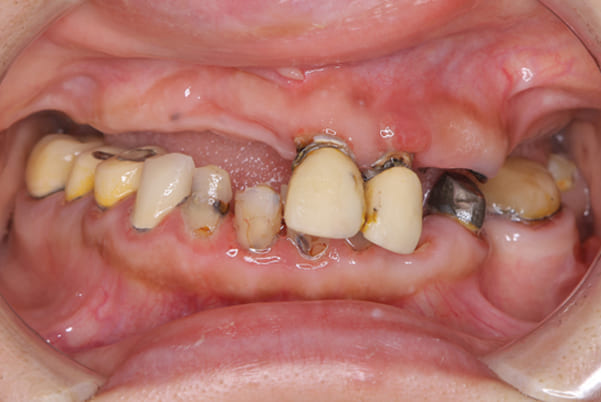

上前歯はブリッジの差し歯により根が折れ炎症を起こしお痛みのある状態でした。

原因は長期使用により下の義歯の歯が削れたことにより、下前歯が上前歯を突き上げ強い力が加わっていたことが根本的な原因と考えられます。

治療前は、奥歯が下がり、かみ合わせが乱れています。適切な入れ歯はそのままのかみ合わせで義歯を作るのではなく治療後のように、前歯から奥歯までのラインが真っすぐ揃った、かみ合わせの面を適切に付与し、よく咬め、残りの歯に負担がかからないかみ合わせとしました。

根のみの7本は虫歯にもなっており歯肉は腫れあがっています。

残りの歯もレントゲンで重度の歯周炎によりぐらぐらな状態でした。

治療前の入れ歯の奥歯は、治療後の義歯と比較しても分かるように、歯が削れ平らになった状態です。

これにより奥歯のかみ合わせは低くなり、前歯のみが強くあたり、かみ合わせにより上の前歯大きな負担がかかっていたことにより、上の前歯が折れたことが考えられます。